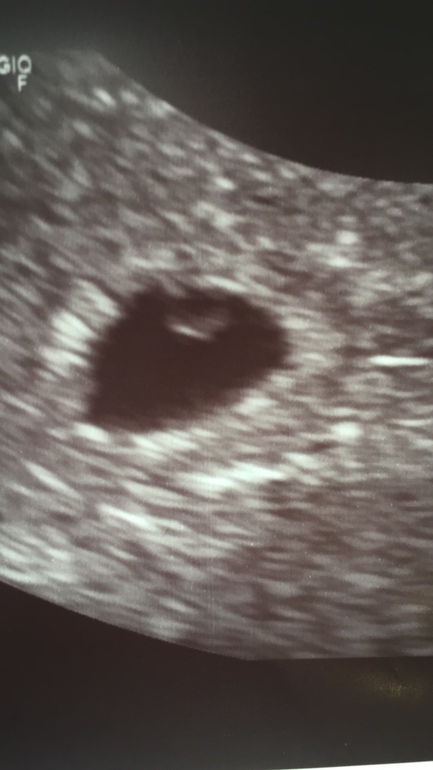

Узи, есть ли надежда?

Всем привет. Посмотрите, пожалуйста, узи сегодняшнее, есть ли ещё надежда? Или готовиться уже к худшему? Может было у кого и все удачно закончилось?

Утром пошла к одному врачу, посмотрев, сказала надежды нет, эмбриона не видит. Если хочешь, говорит, неделю подожди ещё и придёшь посмотрим. Через час пошла к другой. Она и эмбрион показала, и желточный мешок.

В понедельник ходила к одному узисту, она сказала чтобы не надеялась и на повтор в пятницу (сегодня). Во вторник пошла к другой, она поставила неразвивающуюся под вопросом. Утром сходила к той, которая сказала не надеяться, плодное яйцо не выросло вообще, так же 3-4 недели поставила как и было, сказала что если хочу, могу ещё неделю подождать, но смысла не видет. После неё через час пришла к другой (ее результат тут ваставляла), она все увидела и показала.